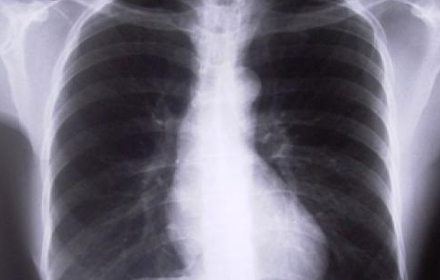

แม้ “วัณโรค” เป็นโรคที่อยู่คู่กับโลกมานาน ทุกวันนี้ยังมีผู้ป่วยที่ยังต้องเผชิญกับความทรมานจากโรคดังกล่าวเป็นจำนวนมาก

เช่นเดียวกับ นายสมบัติ (นามสมมุติ) ชายหนุ่มวัยแรงงานในจังหวัดแถบภาคกลาง ที่ป่วยเป็นวัณโรคชนิดดื้อยารุนแรงมาได้ราว 1 ปี เขาทำงานใช้แรงงานอยู่ในจังหวัดลพบุรี ระหว่างการใช้ชีวิตตามปกติ จู่ ๆ นายสมบัติก็มีอาการของวัณโรคปรากฎขึ้น สิ่งที่นายสมบัติต้องเผชิญไม่ได้มีแต่เพียงอาการไออย่างหนัก น้ำหนักลดจนซูบผอม และมีไข้เวลากลางคืน ทว่าเขายังต้องต่อสู้กับการดื้อยารุนแรง นั่นหมายถึงการดื้อต่อยาที่ใช้รักษาวัณโรคเกือบทุกชนิด ทำให้การรักษายากมาก ใช้เวลานาน ผู้ป่วยมีความเสี่ยงสูงต่อการรักษาล้มเหลว และอาจทำให้ถึงแก่ชีวิต

ข้อมูลจากองค์การอนามัยโลกเมื่อปีพ.ศ.2551 ระบุ ประเทศไทยมีความรุนแรงของผู้ป่วยวัณโรคติดอันดับ 18 จากทั้งหมด 22 ประเทศ ที่ประสบปัญหาอย่างรุนแรงโดยมีการคาดการณ์ว่าในประเทศไทยจะมีผู้ป่วยวัณโรครายใหม่ (ในระยะแพร่เชื้อ) สูงราว 40,000 รายต่อปี และส่วนผู้ป่วยวัณโรค (ทั้งแบบธรรมดา ดื้อยา และดื้อยาชนิดรุนแรง) มีจำนวน 90,000 รายต่อปี ขณะที่มีอัตราผู้ป่วยเสียชีวิตอยู่จำนวน 13,000 รายต่อปี

ในจำนวนผู้ป่วยวัณโรคทั้งหมดจะเป็นผู้ป่วยวัณโรคดื้อยาชนิดไม่รุนแรง ประมาณ 2,900 รายต่อปี และเป็นผู้ป่วยวัณโรคดื้อยาชนิดรุนแรง และรุนแรงมาก จำนวน 145 รายต่อปี